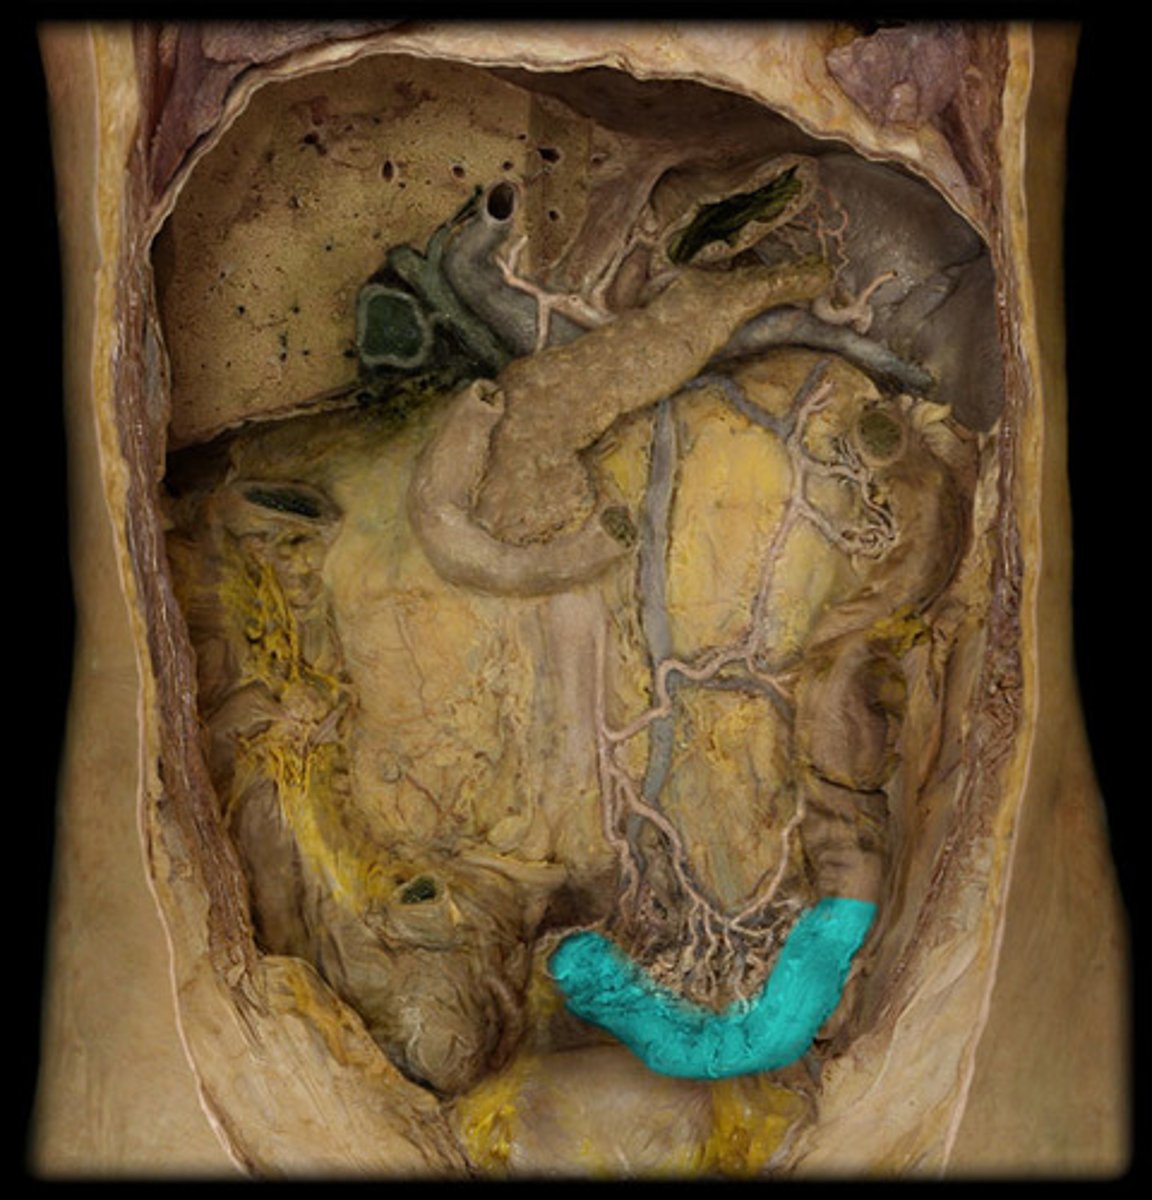

Cecum

What is this?

Vermiform appendix

Attached via mesoappendix